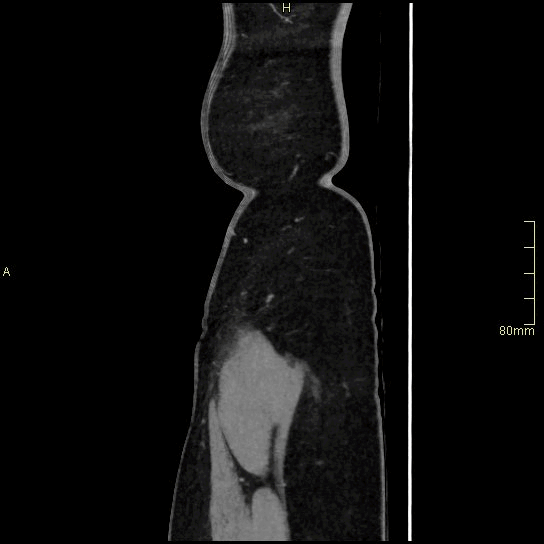

CT Abdomen Venogram- Soft tissue window (coronal)